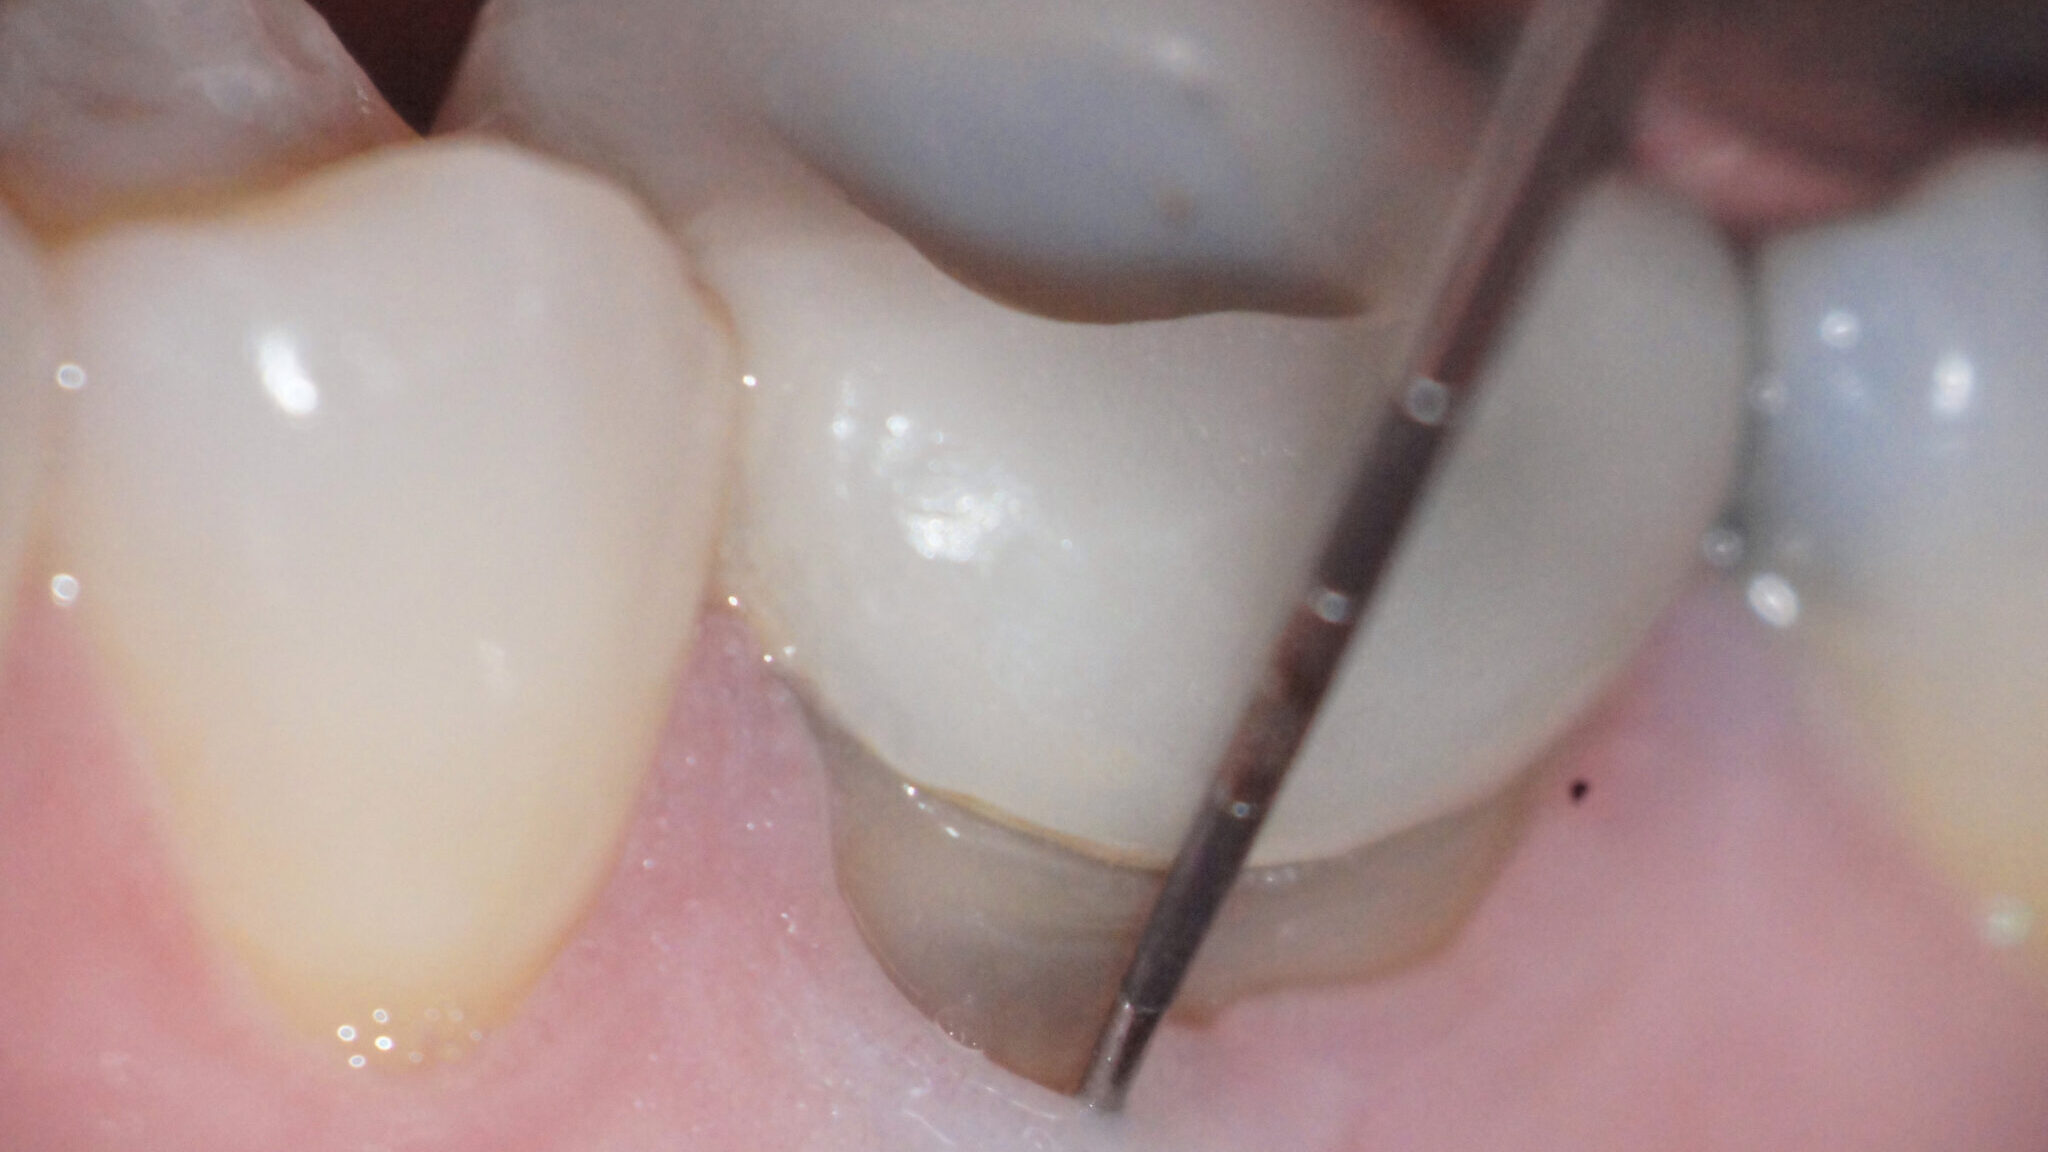

Serota-Fig-4E alternate text for this image

The unceasing innovations and iterations in dental technologies and materials has taken the sophistication of treatment modalities to an historic level. However, when we are focused on the newness, the thrill of the outcome, we fail to pay attention to the purpose of the activity. Case in point; dental implants were initially considered the gold … Read more